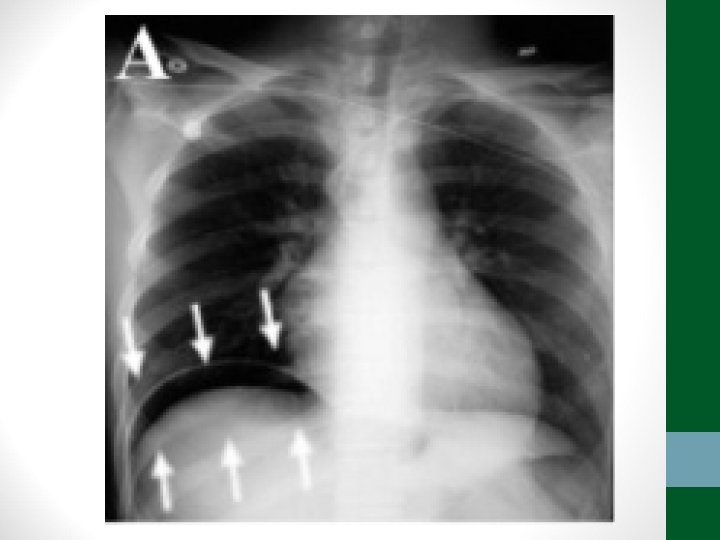

Exames de Imagem • Abdome Agudo Inflamatório: • Radiografia simples de abdome: decúbito, ortostase e cúpulas diafragmáticas • USG Abdome total é diagnóstico na maioria dos casos • TC de abdome com contraste VO e EV se USG não esclarecer ou em forte suspeita de diverticulite aguda ou pancreatite aguda grave

Exames de Imagem • Abdome Agudo Perfurativo: • Radiografia simples de abdome: decúbito, ortostase e cúpulas diafragmáticas • USG Abdome não ajuda! • TC de abdome com contraste VO e EV se Raio-X não esclarecer